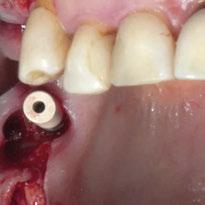

Para ilustrar el proceso, presentamos el caso de una mujer joven diagnosticada de carcinoma adenoide quístico en la región posterior del hemipaladar izquierdo (Figuras 1 y 2). El procedimiento quirúrgico realizado fue una

maxilectomía parcial que incluyó las piezas 24-26 y desde el reborde alveolar hasta la base del cráneo (Figuras 3 y 4). En este caso, la órbita y el globo ocular pudieron ser preservados. La reconstrucción inmediata se realizó mediante un colgajo de músculo temporal homolateral (Figura 5) y el defecto de la fosa temporal fue cubierto mediante una malla de titanio. Posteriormente, la paciente recibió radioterapia (Figuras 6 y 7). 2 años más tarde se diseñó un IS con anclaje en el arbotante nasomaxilar, zona subnasal izquierda

Figura 3. Maxilectomía parcial.

Figura 4. Defecto maxilar tras resección del tumor.

y lo que se pudo preservar del hueso malar. Se añadió una malla sinterizada infraorbitaria para dar volumen a la mejilla y se planificaron dos brazos de conexión que emergieran en las posiciones 24 y 26 de forma subgingival (Figuras 8 y 9). La superficie interna que apoyaba en el hueso era de titanio microrrugoso, y la superficie externa y conectores de titanio pulido y hexágono externo universal (Figuras 10 y 11). La cirugía se hizo bajo anestesia general en infiltración con anestesia local (4% articaína, 1:100.00 epinefrina), levantando el

colgajo cutáneo de la mejilla por vía intraoral, preservando el colgajo temporal para no comunicar con el remanente de la cavidad naso maxilar (Figura 12). Se emplearon 10 tornillos de osteosíntesis de 1,9 mm y la estabilidad primaria obtenida fue excelente (Figura 13)